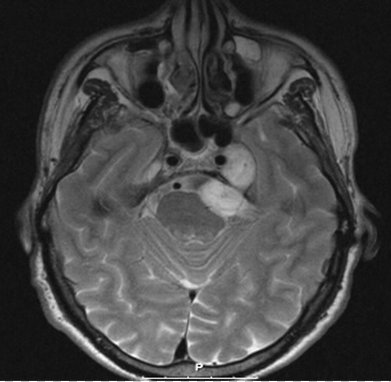

Brain Tumour Causing Left Sided Facial Pain

Brain Tumour Causing Facial Pain

Brain Tumour Causing Pain